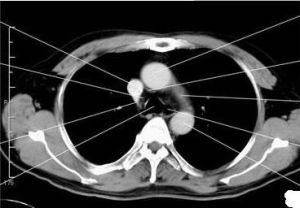

介紹 治療措施後前位,主動脈擴張或延長時,升主動脈和降主動脈向兩側分離,升主動脈外緣可越過心右緣下段,升主動脈與右心房的分界點下移,心更傾向於橫位,降主動脈位於肺動脈...

發病原因 疾病概述 症狀體徵 病理生理 診斷檢查、主動脈和肺動脈等的情況得出全面的印象,並可觀察胸部有無其他異常改變,從而作出...動脈、主動脈弓上緣與脊椎前緣構成;弓下有主動脈窗,其中包括有氣管分叉、左主支氣管和左肺動脈。主動脈降部見於心影后方,部分與脊椎重疊。 記波攝影...